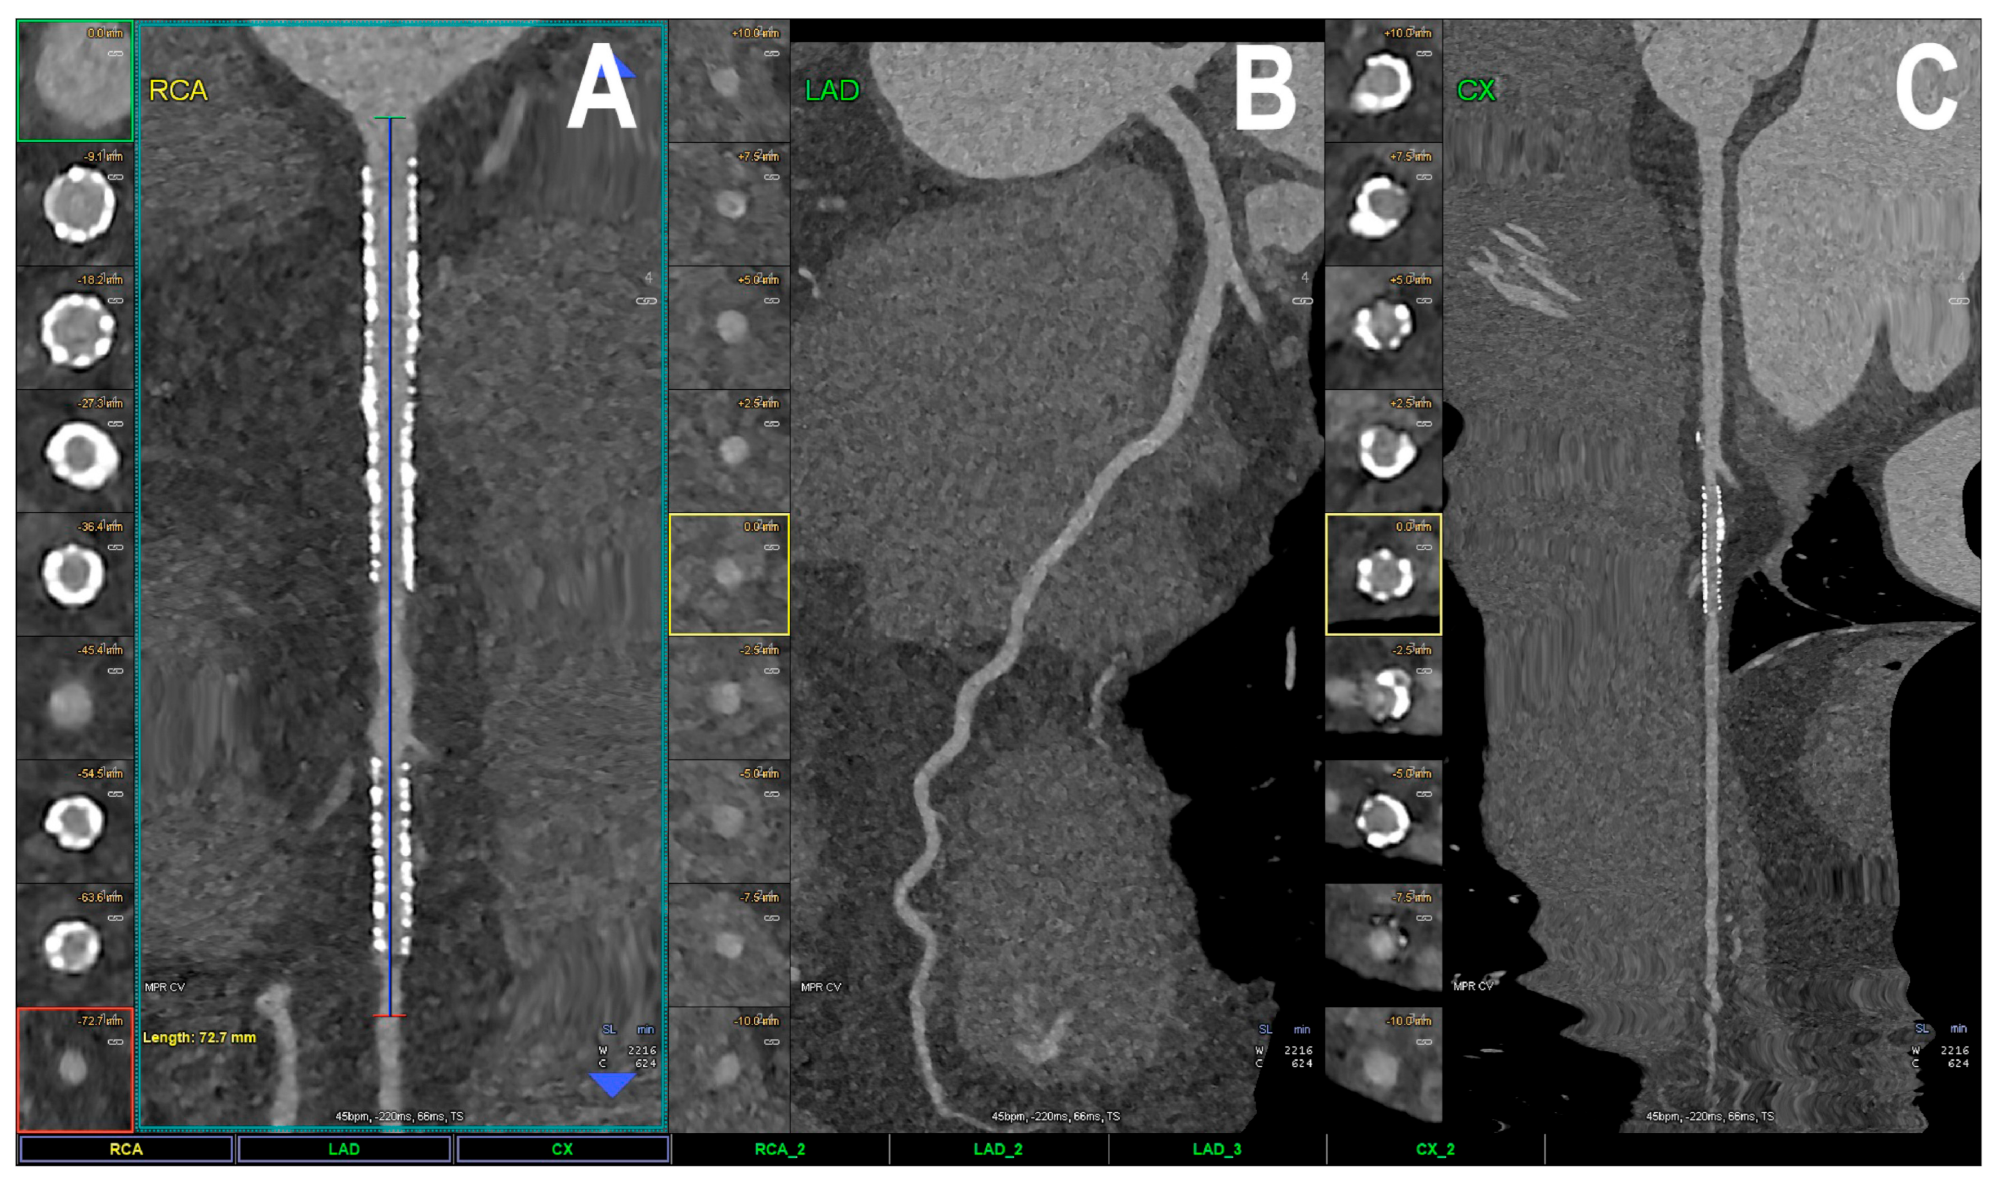

- Sun, Z.; Ng, C.K. Artificial intelligence (enhanced super-resolution generative adversarial network) for calcium deblooming in coronary computed tomography angiography: A feasibility study. Diagnostics 2022, 12, 991. [Google Scholar] [CrossRef]

- Sun, Z.; Ng, C.K. Finetuned super-resolution generative adversarial network (artificial intelligence) model for calcium deblooming in coronary computed tomography angiography. J. Pers. Med. 2022, 12, 1354. [Google Scholar] [CrossRef]